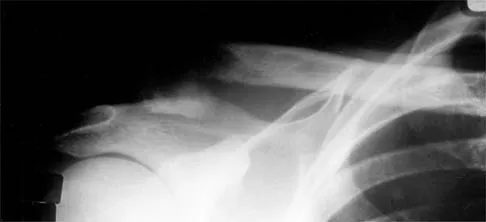

A 25-year-old student sustains the injury shown in Figures 13a through 13c after falling off a curb. Initial management should consist of

Explanation